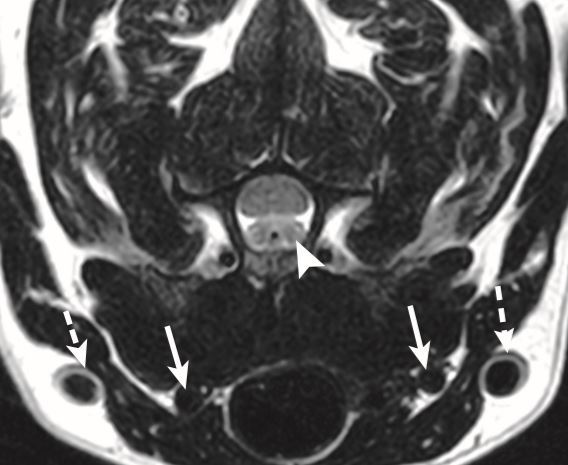

What artifact is this?

A

CSF flow artifact causing a pseudolesion

What is this artifact?

Pulsatility artifact/ghosting

22

Q

What direction is the pulsatility artifact seen in?

Phase encoding and only in this direction